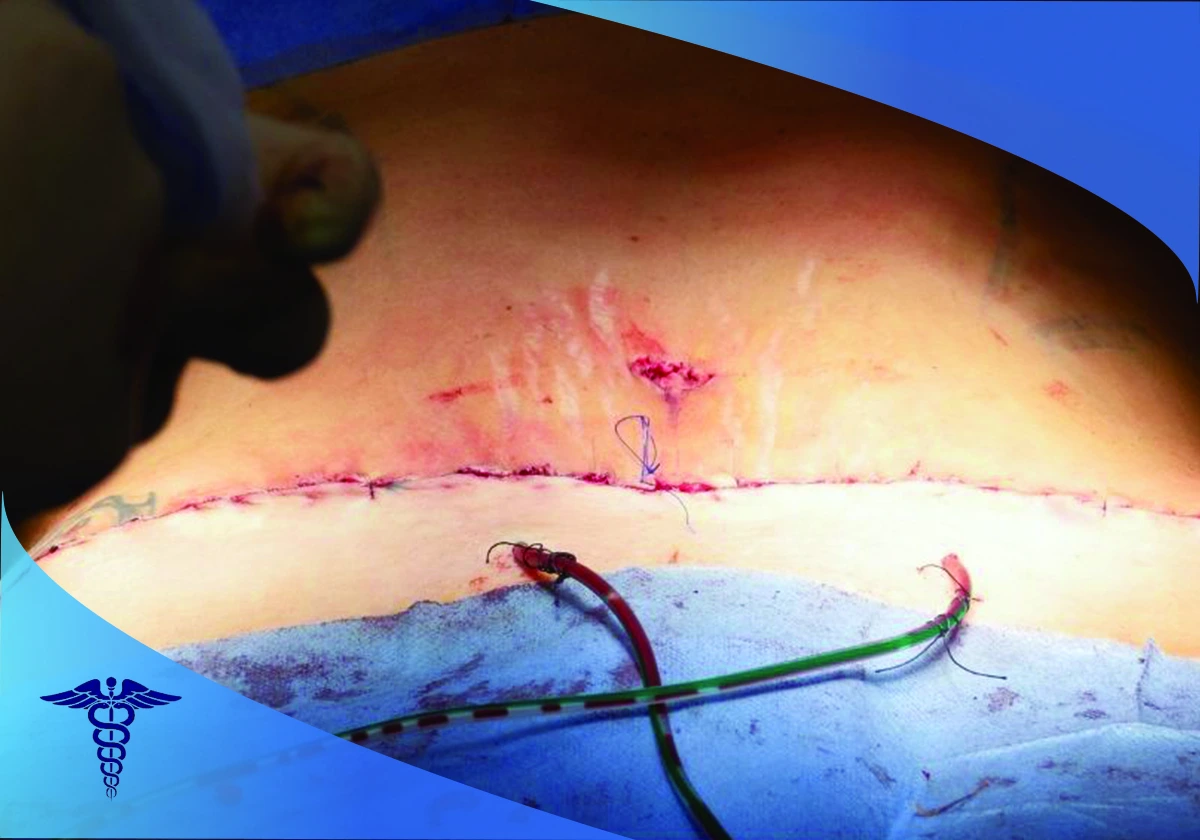

بخیه و پانسمان

پس از برداشت چربی و پوست اضافی، پوست باقیمانده کشیده شده و نواحی برش داده شده بخیه و سپس پانسمان می شوند. مهارت پزشک جراح در این مرحله در کاهش جای زخم و بخیه ها و در نهایت زیبایی شکم بسیار تعیین کننده و کارساز است.

پس از انجام عمل جراحی ابدومینوپلاستی در شیراز، بیمار باید دوره نقاهت خود را در حدود ۶ هفته طی نماید. در این مدت عمل به توصیه های جراح و مراقبت های پس از جراحی در نتیجه حاصله بسیار موثر است. پوشیدن گن طبی در این مرحله به کاهش تورم و التهاب و همچنین ایجاد فرم زیباتر در ناحیه شکم کمک می کند.

چه زمانی پس از عمل می توان دوش گرفت؟

اگر از درن (لوله های تخلیه) استفاده شده، باید صبر کنید تا پزشک آن ها را خارج کند. حدودا دو روز بعد از برداشتن درن ها می توان دوش گرفت. اگر درن نداشته باشید، چهار روز بعد از عمل می توانید استحمام کنید.